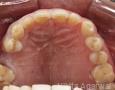

Baseline